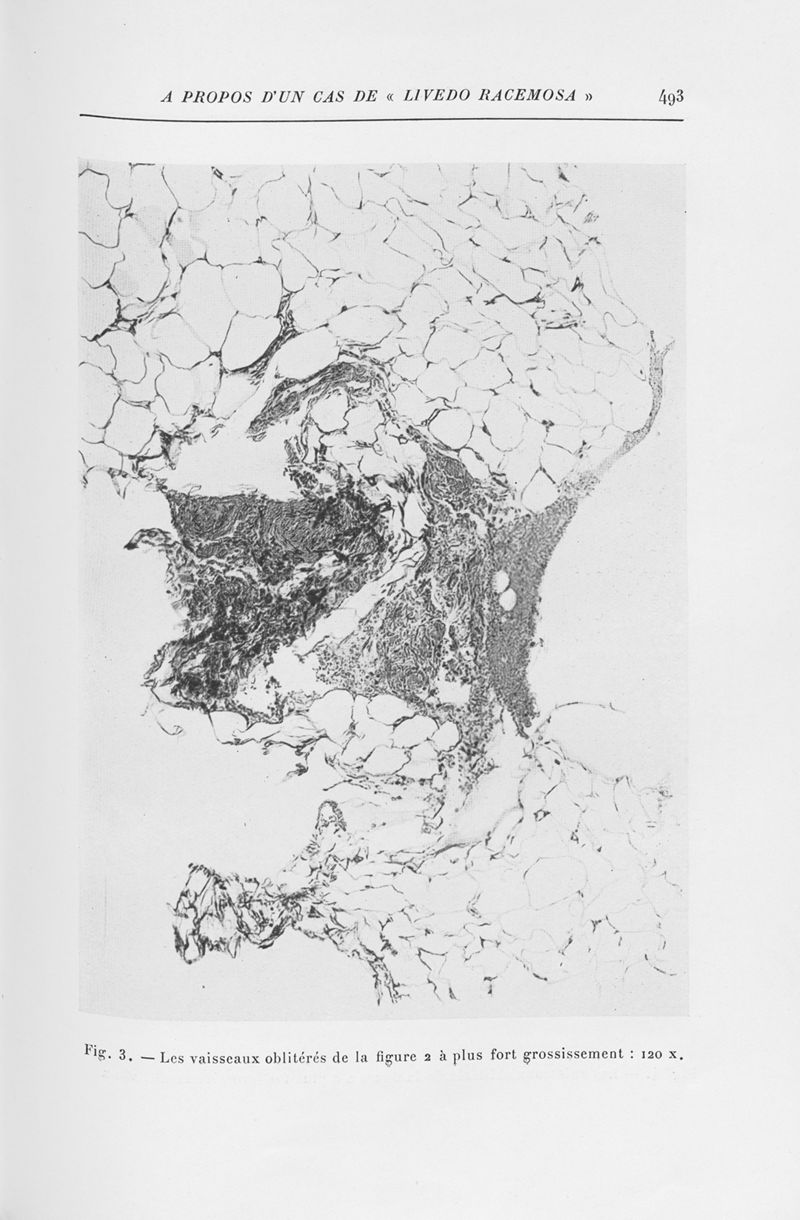

Annales de dermatologie et de syphiligraphie

7ème série, tome V. - Paris : Masson, 1934.